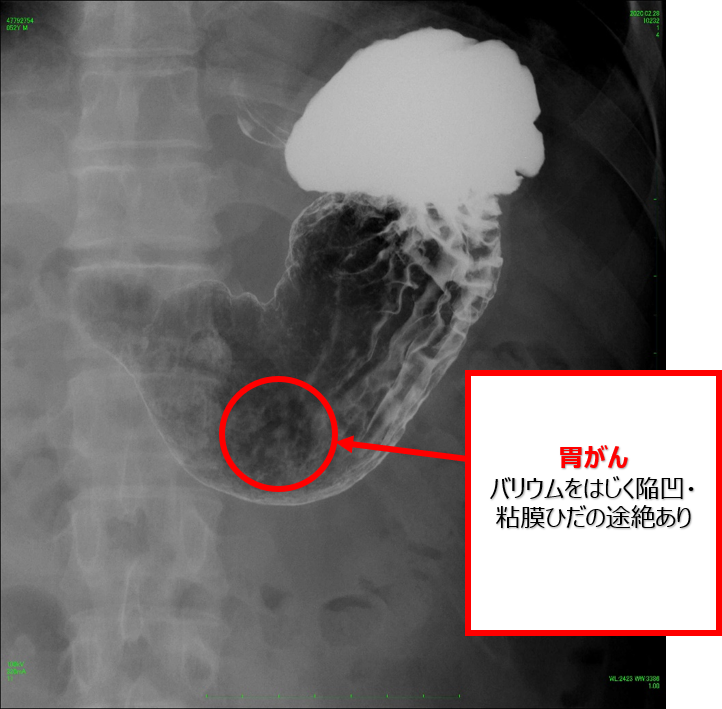

●食道・胃の造影検査

食道や胃を撮影するには造影剤(主にバリウム)を飲用して検査を行います。まず、一時的に胃腸の動きを抑える注射を打ちます。その後、造影剤と発泡剤(食道と胃を膨らませる薬)を飲み、体の向きを色々と変えながら造影剤を胃の粘膜に塗り付けて撮影します。

大腸造影(バリウム)

大腸の粘膜にバリウムを付着させて、管から空気を送り込んで大腸を膨らませて撮影します。